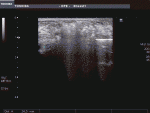

5)焼灼範囲:腫瘍縁から1cmのマージンを目標とし,ニードルポジションを設定する.焼灼中の超音波画像にて腫瘍の不明瞭化とマイクロバブルの範囲を確認し,十分な焼灼エリアを確保する(図7).